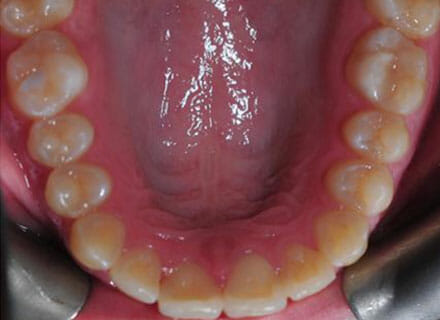

In this case, the upper incisors had a pushed back appearance and they were twisted. the smile was narrow – when the patient smiled the sides of the smile were in shadow. we used clear brackets to gently untwist and straighten the front teeth while widening the upper arch/jaw to broaden the smile. this patient was beaming for the first time in just 12 months.